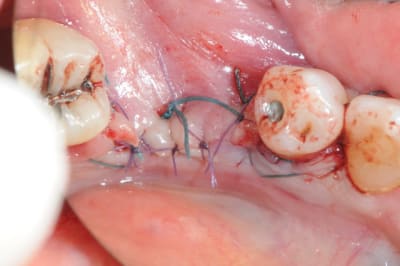

> 1. tes vis ne sont pas positionnées comme il faut.

> 2. tes vis sont trop enfouies

> 3. tes sutures ne sont pas assez profondes. comme je te le disais à l'ADF, tu

> dois être à au moins 1 cm de la berge.

photo

1-2 positionnement des vis pas tout à fait pareil que sur le soft de planification...

ici, les perforations sont beaucoup plus grosses car l'os était nettement moins bien vascularisé et beaucoup plus corticalisé que dans le 1er cas

3- fixation sur la paroi vestibulaire

4- comblement en abondance avec autogène et bioos

5- sutures (patiente vu aujourd'hui, ça tient)